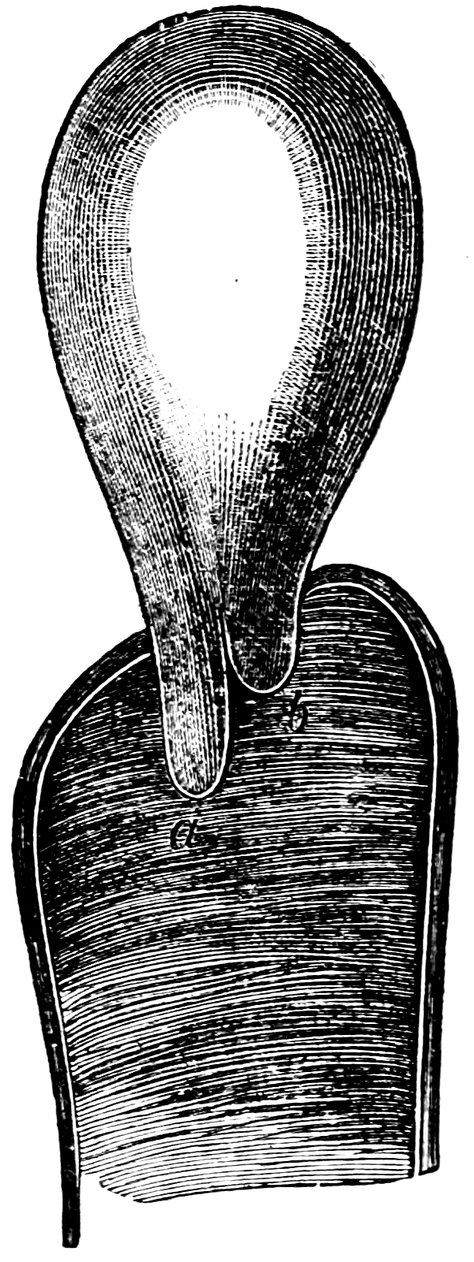

| 41. | A. Septate Hymen in which defloration has been effected through one of the Apertures. U. Urethra. Cl. Clitoris. H. Cicatrized Margin. C. Septum. B. Lateral view of Septum | 70 |